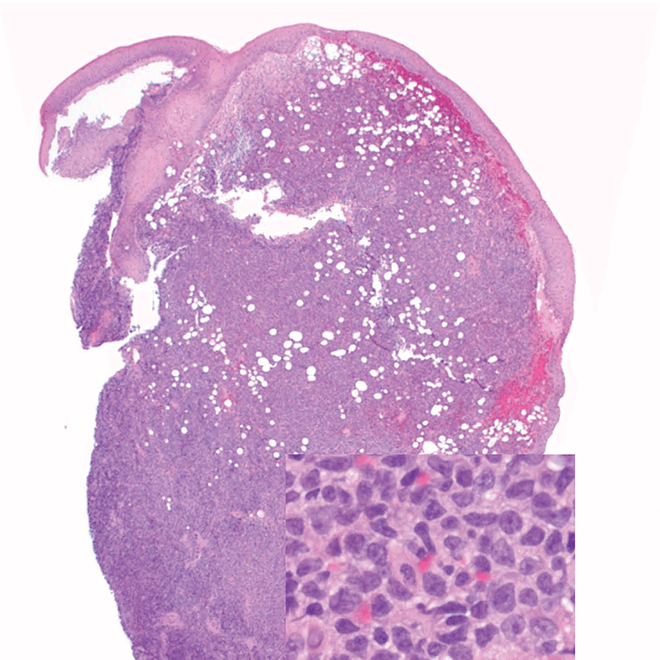

Skin

Punch biopsy of a skin lesion showing BPDCN (H&E stain, x40) and (inset) medium-sized malignant cells spare the epidermis (H&E stain, x1000).11

H&E, hematoxylin and eosin.

Main morphologic features of BPDCN biopsy

• Diffuse, monomorphic infiltrate1

• Medium-sized blast cells with irregular nuclei1

• Fine chromatin1

• At least 1 small nucleolus1

• Malignant BPDCN cells do not typically infiltrate the epidermis4